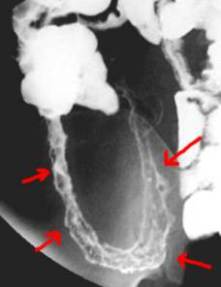

Typical appearance of Crohn's disease involving terminal ilem with ulcerations noted on barium small bowel examination (red arrows) .

Photo credit: Jeffrey Dach MD

This chronic inflammatory disease of the small bowel is notably difficult to treat, but in a 2007 publication, Dr. Jill Smith wrote an article entitled “Low dose naltrexone therapy improves actve Crohn’s disease“, reporting that 12 of her 17 patients went into remission and all but two experienced some benefit from the therapy. Before and after treatment colonoscopy photos showed impressive results with inflammation cleared in the bowel mucosa. The oral 4.5 mg dose of Naltrexone was given in the evening for 12 weeks.